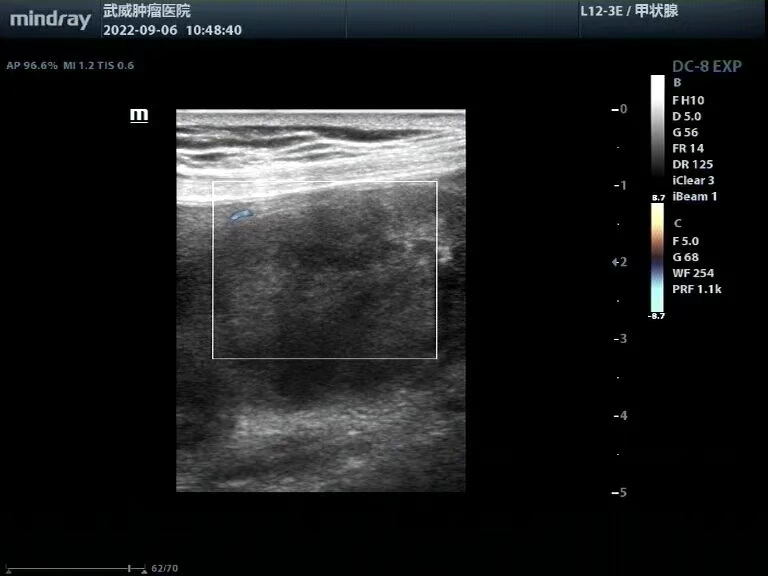

腹腔探查:腹主动脉旁见数个低回声肿物,边界清,回声欠均匀,其内见短条状血流信号,最大约23x16mm(图2)。

图2 腹主动脉旁的多发肿大淋巴结

图3 高频超声可见胆囊前壁完整,未浸润肝脏